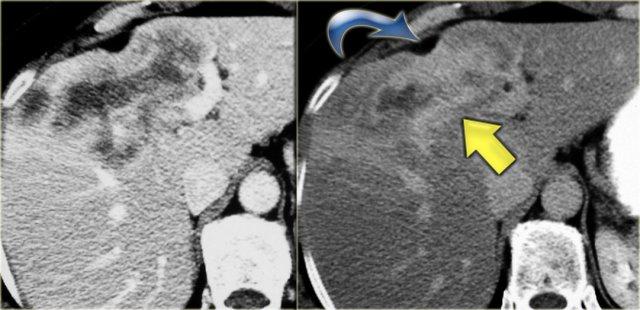

Bên trái là hình ảnh CT của cùng bệnh nhân.

Lưu ý dấu hiệu chấm trung tâm và tổn thương theo phân thùy.

Bệnh nhân này có xơ gan kèm lách to do tăng áp lực tĩnh mạch cửa.

Giãn ống mật ngoài gan hiện diện trong 53% các trường hợp, thứ phát do viêm đường mật và sự di chuyển của sỏi hoặc bùn mật.

Đây là các dấu hiệu thứ phát, không phải là một phần của bệnh nguyên phát.

Bên trái là hình ảnh bệnh nhân với các ống mật giãn kèm sỏi trong ống (mũi tên)

Các dấu hiệu bao gồm:

- Thận xốp tủy kèm hình thành sỏi (mũi tên đỏ)

- Giãn nhẹ ống mật (mũi tên xanh dương)

- Khối giảm tỷ trọng dạng tròn ở thùy gan phải

Khối ở thùy gan phải được xác định là áp xe.

Cần lưu ý rằng áp xe gan trong giai đoạn sớm có thể có hình ảnh khá đặc.

Trong chẩn đoán phân biệt, chúng ta cũng cần xem xét khả năng u tân sinh, vì bệnh nhân mắc bệnh Caroli có nguy cơ tăng cao phát triển ung thư biểu mô đường mật.

Cuối cùng, nếu có xơ hóa đáng kể và toàn bộ gan bị ảnh hưởng, những bệnh nhân này sẽ tiến triển thành xơ gan.

Bệnh nhân bên trái đã tiến triển suy gan nặng và được phẫu thuật cắt gan.

Lưu ý tình trạng giãn ống mật trong gan, lách to và giãn các tĩnh mạch bàng hệ.

Trên bệnh phẩm cắt bỏ có dấu hiệu chấm trung tâm (mũi tên xanh dương) và một ổ mủ nhỏ (mũi tên vàng).